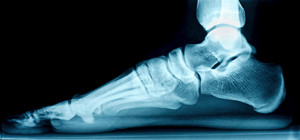

What Is Causing My Heel Pain?

If you are suffering from heel pain, it could be a result of plantar fasciitis, which is the leading cause of heel pain. Plantar fasciitis occurs when the band on the bottom of the foot that connects the toes to the heel, called the plantar fascia, becomes inflamed. This commonly occurs in those who have problems with their arches, such as flat feet or overpronation. Common plantar fasciitis symptoms include pain in the bottom of the heel or the arch of the foot, pain that increases over time, pain that is worse when getting up in the morning, and swelling on the bottom of the heel. If you believe that you are suffering from plantar fasciitis, it is important to visit a podiatrist. A podiatrist will be able to provide a proper diagnosis and treatment method that may include medicine, taping/strapping, orthotics, casts, therapy, or surgery.

What Is Plantar Fasciitis?

Plantar fasciitis is one of the most common causes of heel pain. The plantar fascia is a ligament that connects your heel to the front of your foot. When this ligament becomes inflamed, plantar fasciitis is the result. If you have plantar fasciitis you will have a stabbing pain that usually occurs with your first steps in the morning. As the day progresses and you walk around more, this pain will start to disappear, but it will return after long periods of standing or sitting.